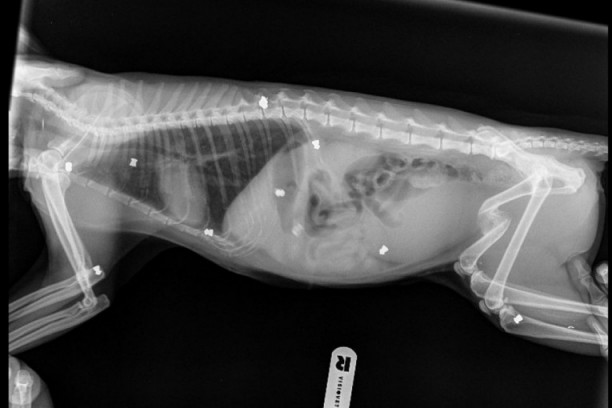

Hrabra i umiljata maca nazvana Šefica iz Crne Gore je dovedena u Beograd, gde je operisana, a tom prilikom je u njenom telu pronađeno čak devet dijabola!

Nehumana osoba koja je pucala je momentalno paralizovala mačku jer se jedan metkić zario u kičmu, ali su dobri ljudi NVO Ruka-Šapi, uspeli da je odvedu kod veterinara, koji ju je operisao i uklonio dijabole, ali ne sve.

- Nisu izvađene sve dijabole, ali jeste većina. Dve su suviše duboko u telu, pa bi intervencija njihovog uklanjanja bila sama po sebi rizična. Zato je preporučeno da se ipak ne diraju, jer ne prave smetnju, iako je jedna u trbuhu, a druga u grudnom košu (nekako je imala neku ludu sreću da ne oštete organe). Maca bez trunke straha, slabosti, stojički noseći ožiljke i teške rane može samo da dobije ime Šefica - da nam svima kaže da posle svakog pada treba ustati i nastaviti dalje, još jače i hrabrije. Ona je sad pred najtežim izazovom, a da li će ga prebroditi umnogome zavisi od svih nas i ne smemo da je ostavimo samu! Šansu da opet stane na svoje noge dobila je u veterinarskoj ambulanti Spina. Oštećenje nije malo, ali veterinar dr Milan Matić je potvrdio mišljenje i dr Aleksandre Riso iz Montveta da ona nikako nije kandidat za eutanaziju jer po neurološkim znacima ona može da se oporavi! Njen oporavak je tek počeo i pred njom su meseci strpljenja, vežbi i potporne terapije, a zatim i traženje doma jer na mesto gde su godinama pucali na nju ne može i ne sme da se vrati. Trenutno se oporavlja kod divne Eme Petrović, bez koje ništa od ovog ne bi bilo moguće - kaže Kristina Radinović, iz NVO Ruka-Šapi.